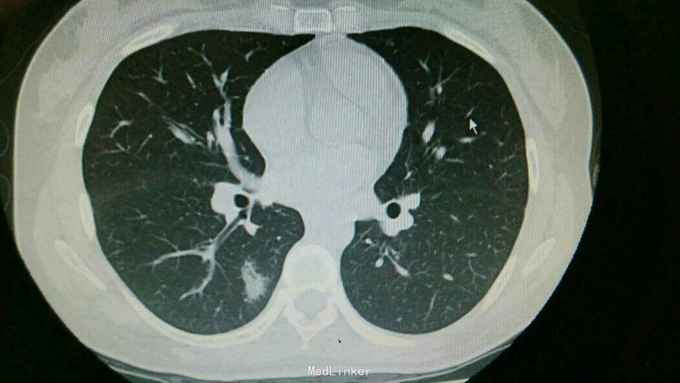

查体:双肺呼吸音粗,右肺可闻及湿罗音, 余无特殊 辅查:血常规示中性粒细胞稍高。胸片:右上肺野炎性病变。肺炎支原体抗体滴度1:640。胸部CT:双肺炎症。

诊断:支原体肺炎。 治疗,予以阿奇霉素抗感染,止咳化痰等处理。复查胸片提示炎症较前好转。